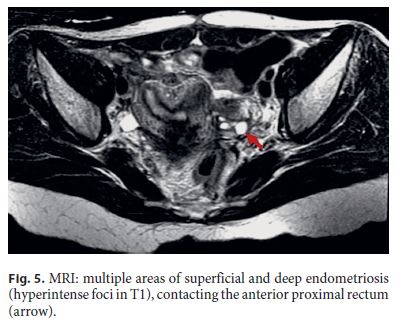

Three months after surgery, the patient was asymptomatic. For endoscopic reassessment before intestinal transit restoration, a rectosigmoidoscopy was performed up to 12 cm from the anal margin. At this level, edema was detected and the mucosa was hyperemic with a tight stricture (Fig. 4). Pelvic magnetic resonance imaging (MRI) revealed several hyperintense foci in T1, corresponding to multiple areas of superficial and deep endometriosis, one of them in contact with the anterior proximal rectum, with no large nodules in the anastomotic area (Fig. 5).